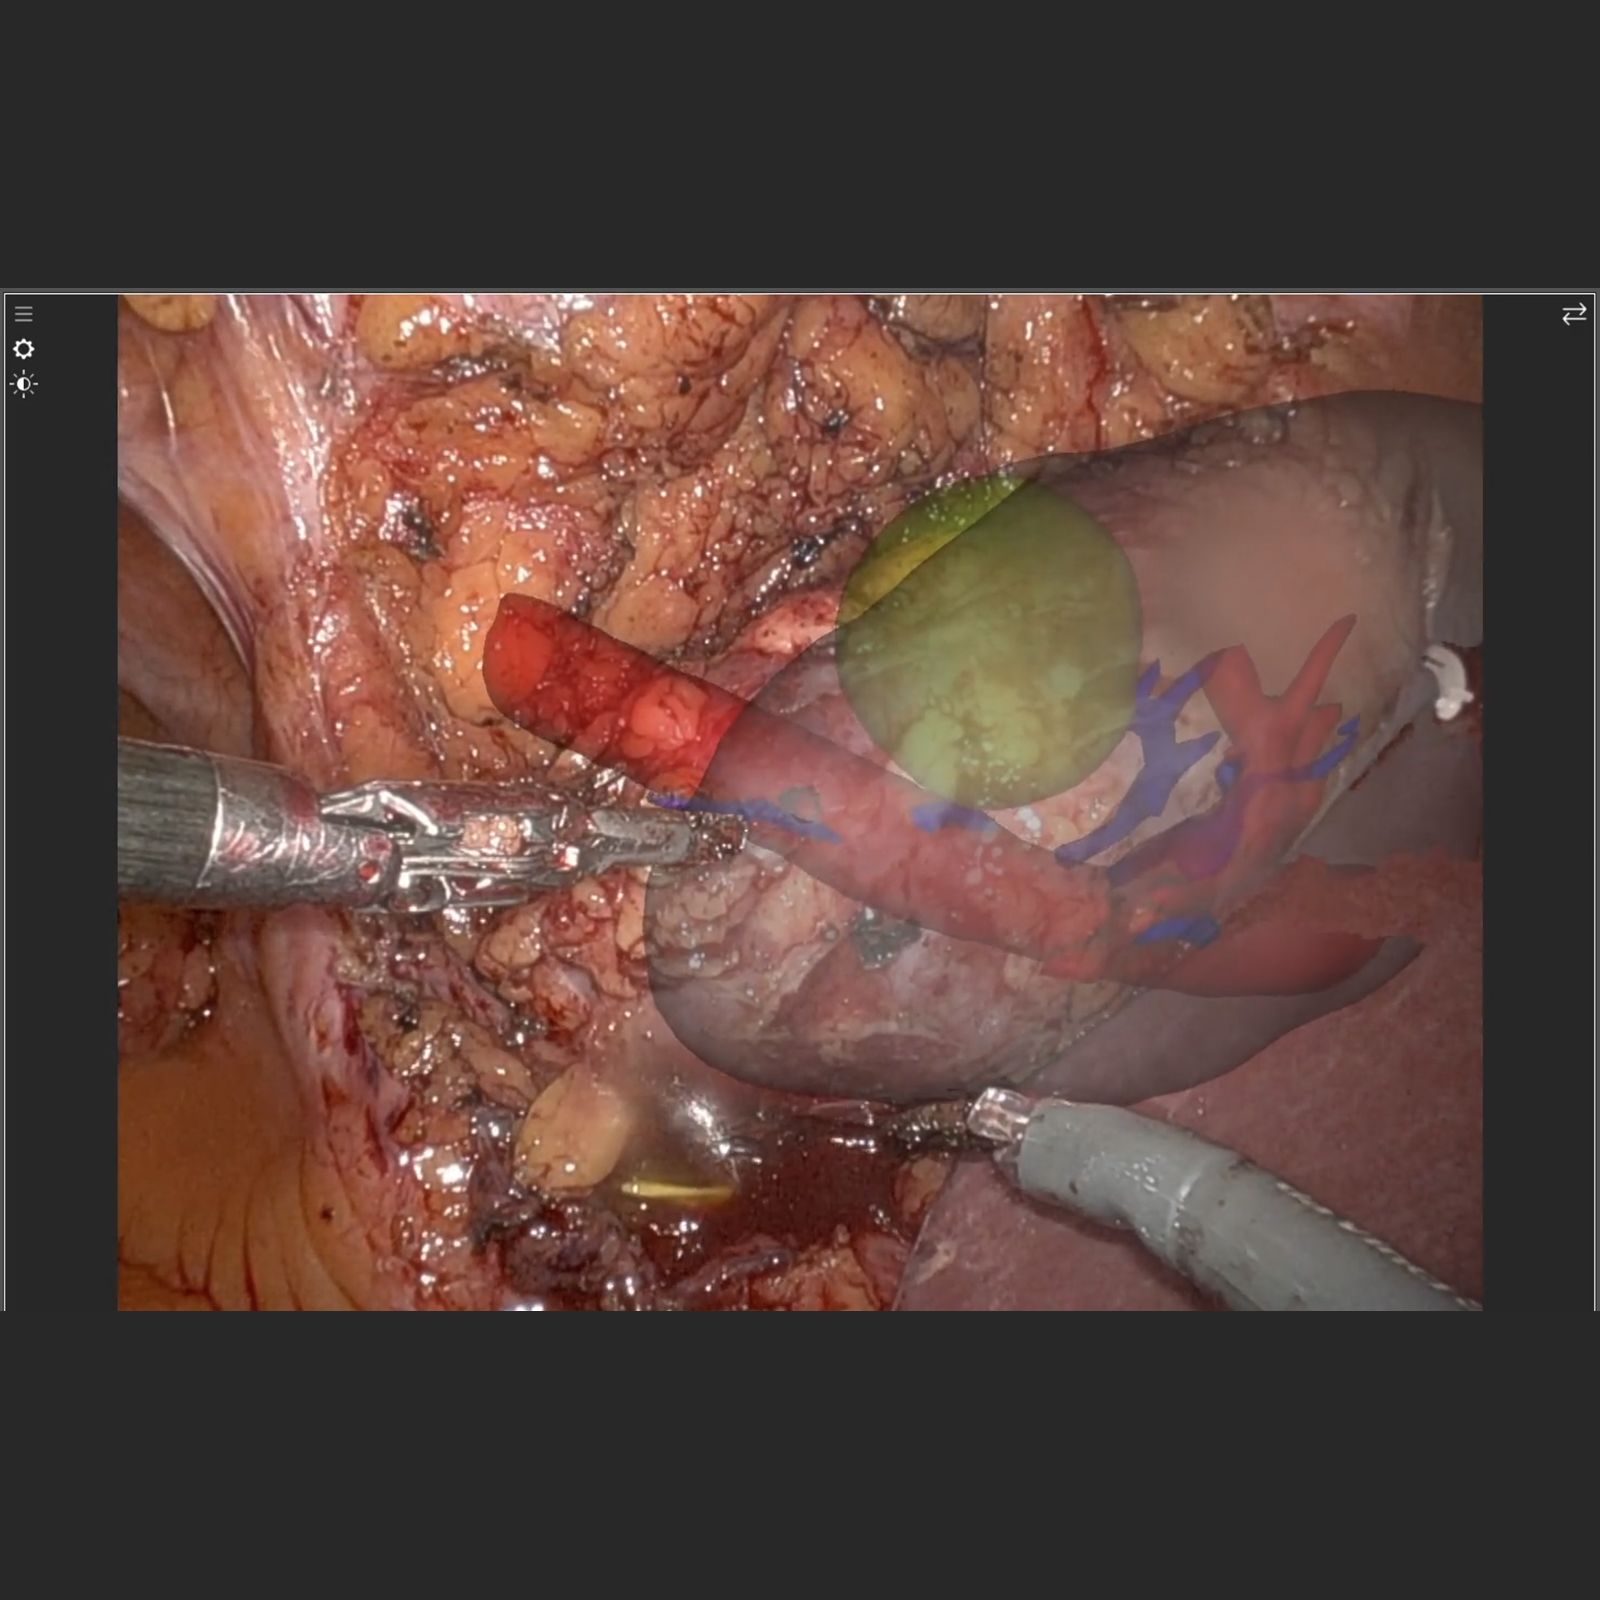

Endoscopic Tissue Tracking

This video shows how different features, including stereo depth reconstruction, optical flow computation, feature tracking and Holoscan integration come together to enable innovative medical applications. For this video we specifically worked with our clinical partners from Orsi to track a pre-op kidney organ segmentation in the endoscopic video as the camera is moved and the tissue interacted with.